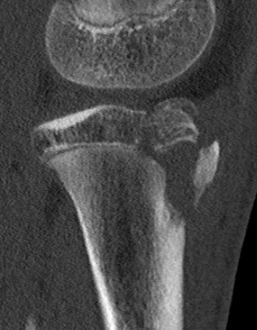

CT / MRI scan

CT scan - ensure fracture doesn't involve the physis / disrupt articular surface

MRI scan - patella tendon injury / periosteal sleeve avulsion

Type IB

Type IIB

Type III

Comminuted Type III